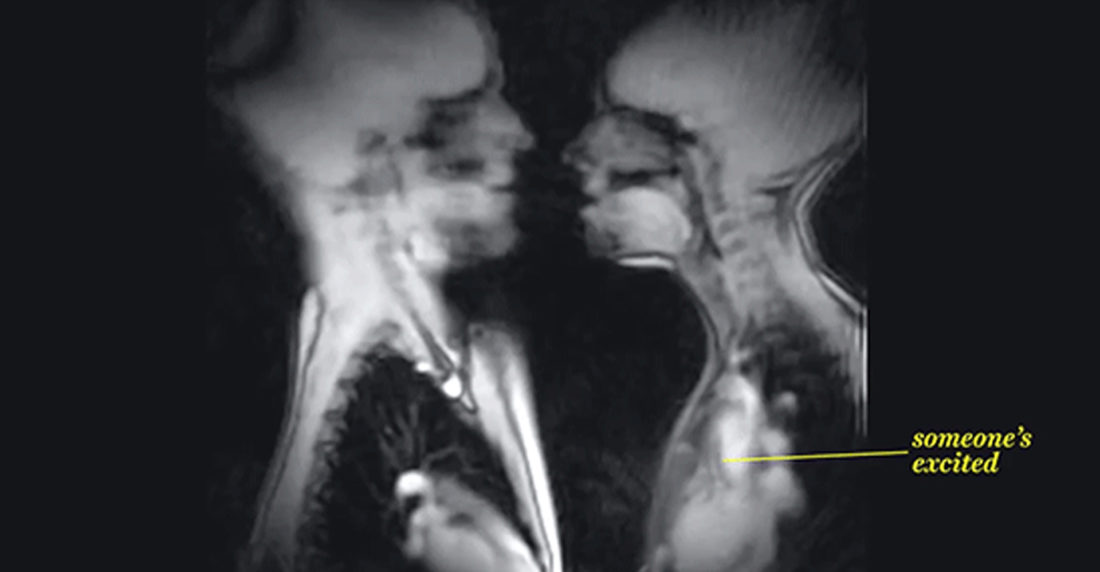

Así se ve un coito en una máquina de resonancia magnética

Además de mostrarnos otras funciones normales del cuerpo en forma de moléculas y protones, no podía faltar una demostración de contacto sexual

Una máquina de resonancia magnética por imágenes -MRI por sus siglas en inglés – utiliza poderosas ondas magnéticas y ondas de radio para ilustrarnos el interior de nuestros cuerpos.

Este video publicado por el portal Vox nos muestra todo lo que pasa dentro de nuestro cuerpo en imágenes. Pero si te detienes en la mitad podrás ver cómo se ve realmente el movimiento de un coito. Y también un beso con lengua.

La anatomía no falla.